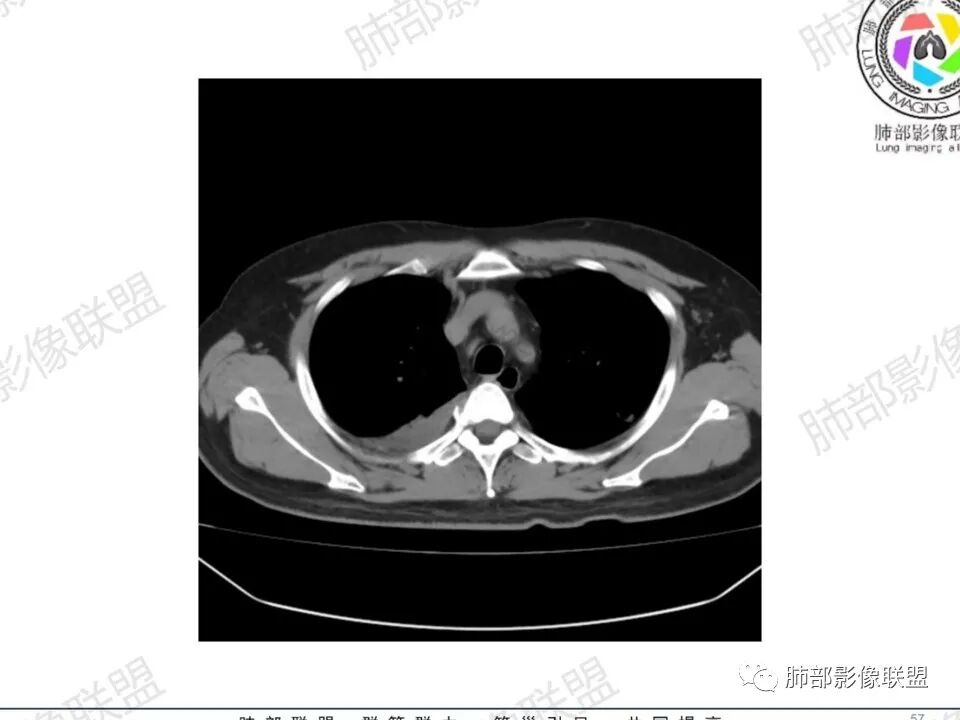

双肺多发结节,胸膜下为主,部分可见空洞。左肺上叶尖后段结节较大,分叶毛刺,周围可见长条索及小斑片影,内空洞比较光滑,内侧壁可见支气管通过。右肺下叶后基底段不张实变,后侧积液,右侧水平裂积液,右侧膈胸膜纵膈胸膜增厚积液,右侧侧胸膜肥厚,考虑1:一元金葡。2二元:金葡,左肺上叶结核。

男,45岁,左手指红肿疼痛两天,右侧胸壁疼痛伴发热12小时入院。患者急性起病,胸部CT示双肺多发结节,部分伴空洞,空洞壁较光滑,右侧胸腔积液,考虑感染性病变,金葡菌加SPE可能

中年男性,左手中指及胸壁疼痛伴发热来诊,影像见双肺多发结节,胸膜下分布为主,部分结节可见空洞,边缘模糊。左肺上叶尖后段结节较大。右肺下叶后基底段不张实变,右侧叶间裂及右侧胸腔积液,右侧侧胸膜肥厚。考虑金葡菌感染,血播SPE。

两肺多发结节空洞,随机分布,右肺下叶部分病灶实变并胸膜腔少量积液,有皮肤破溃,手指疼痛,发热,考虑感染性变,金葡可能性大。

胸膜下为主多发结节,边缘光滑

伴随楔形影,支气管壁不增厚

空洞内壁光滑,偏心厚壁空洞,张力高

胸水,部分包裹

支持血道来源感染性病变,金葡菌肺炎首选